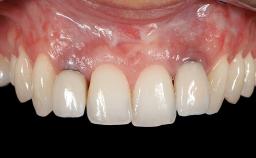

Early Implant Placement, Contour Augmentation, and Autologous Connective-Tissue Graft Using a Tunneling Technique to Replace an Upper Incisor with Generalized Gingival Recession

Variations in soft-tissue volume, evidenced either by an overabundance (Evian and coworkers 1993; Levine and McGuire1997; Dolt and Robbins 1997) or by a deficiency of soft or hard tissue can complicate implant-supported rehabilitations in the esthetic zone (Lorenzana 2008; Lorenzana and coworkers 2009). The present case illustrates the replacement of a failing upper left lateral incisor complicated by generalized severe gingival recession in the esthetic zone.